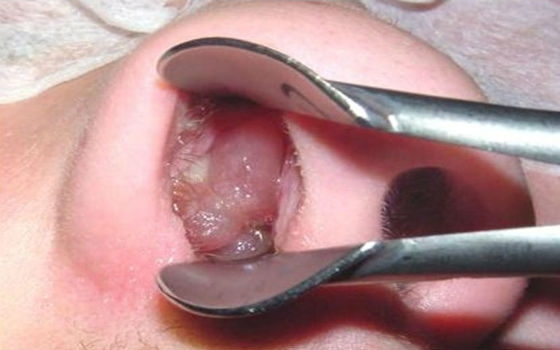

?У дитини аденоїди можуть виглядати як безформна опухолеподобная маса з горбистою поверхнею.?

Такі разращения викликають безліч неприємних проявів і називаються аденоїдами. Побачити їх без спеціального дзеркала важко. Поруч зі склепінням носоглотки з лімфоїдною тканиною розташовані гирла слухових труб і отвори носових ходів.

- ендоскопічного дослідження за допомогою оптичного устаткування, що дозволяє в деталях розглянути вегетації, визначити їх ступінь і наявність запального процесу;

Розрослися аденоїди у дитини в носі зможе виявити ЛОР-лікар. Після опитування доктор зробить первинний огляд: перевірить горло і носові ходи (передня риноскопія), за допомогою дзеркала на тримачі загляне в носоглотку (задня риноскопія), отоскопом оцінить стан вушних проходів.

Точну діагностику гарантує ендоскопічний огляд. Техніка його проведення наступна:

- за 15 хвилин робиться проба на знеболююче;

- в носову порожнину впорскується судинозвужувальний препарат і анестетик;

- вводиться дуже тонкий дріт з камерою (ендоскоп).